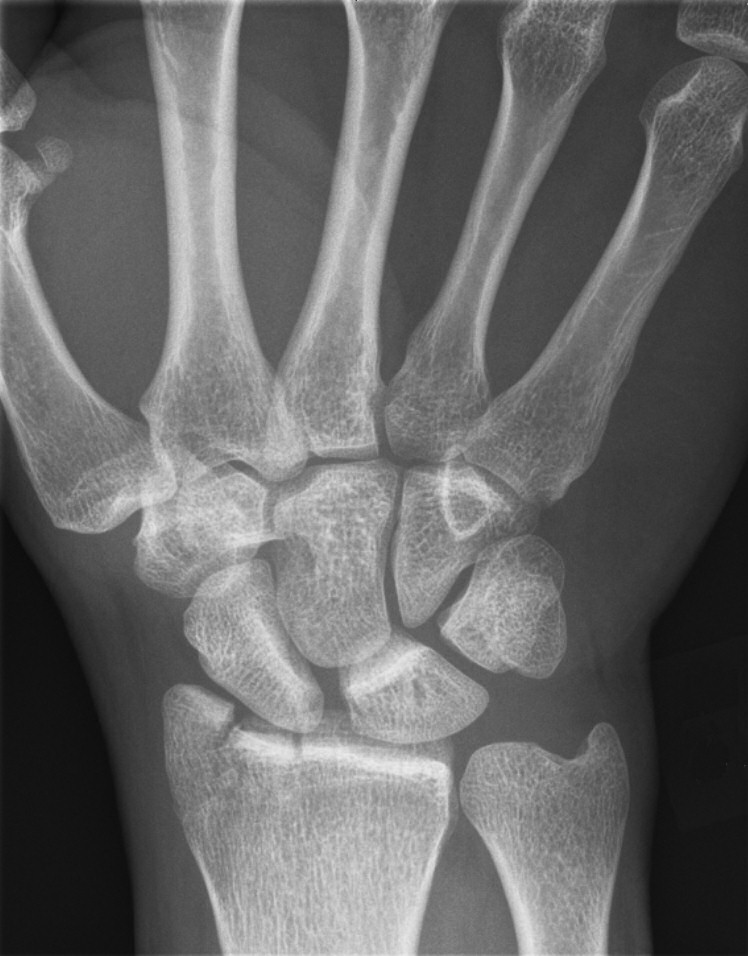

- Die-punch: inpressad ledyta efter kompression vid axialt våld.

Die-punch-fraktur i distala radius